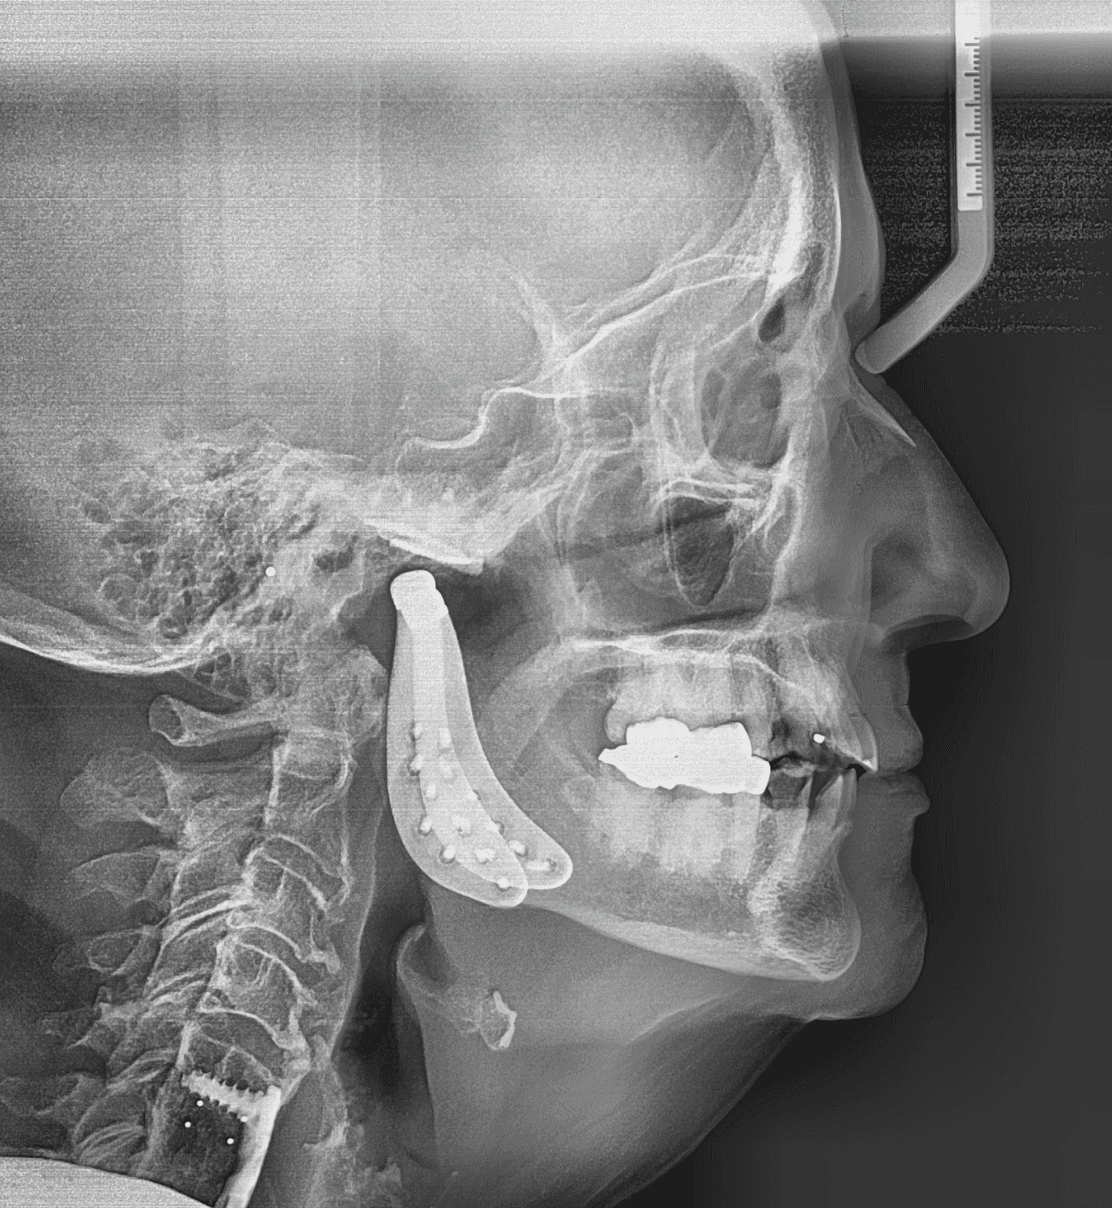

Diganosis: Complex pre-restorative treatment to open bite, mild to moderate upper and lower crowding, incisal wear in both arches

Final results

X-RAYS